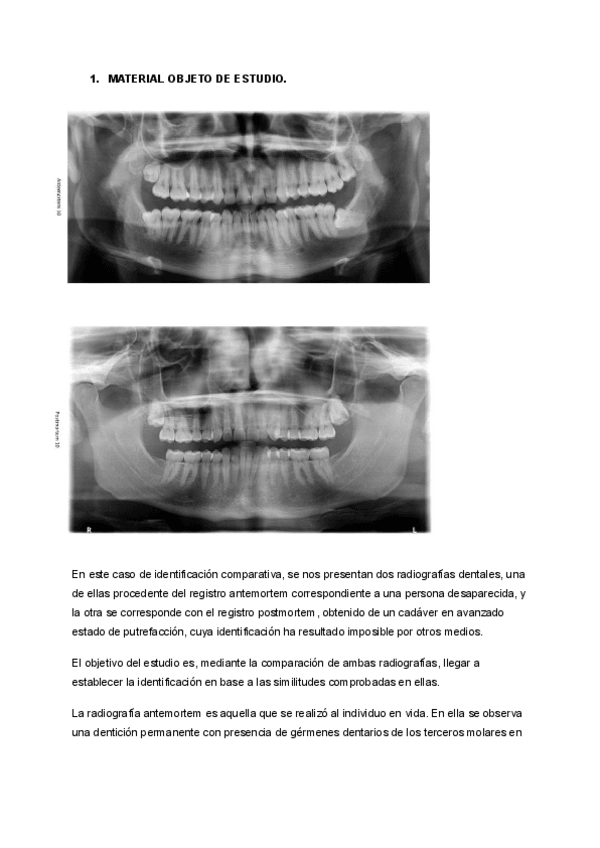

PRACTICA-3-Identificacion-comparativa.pdf